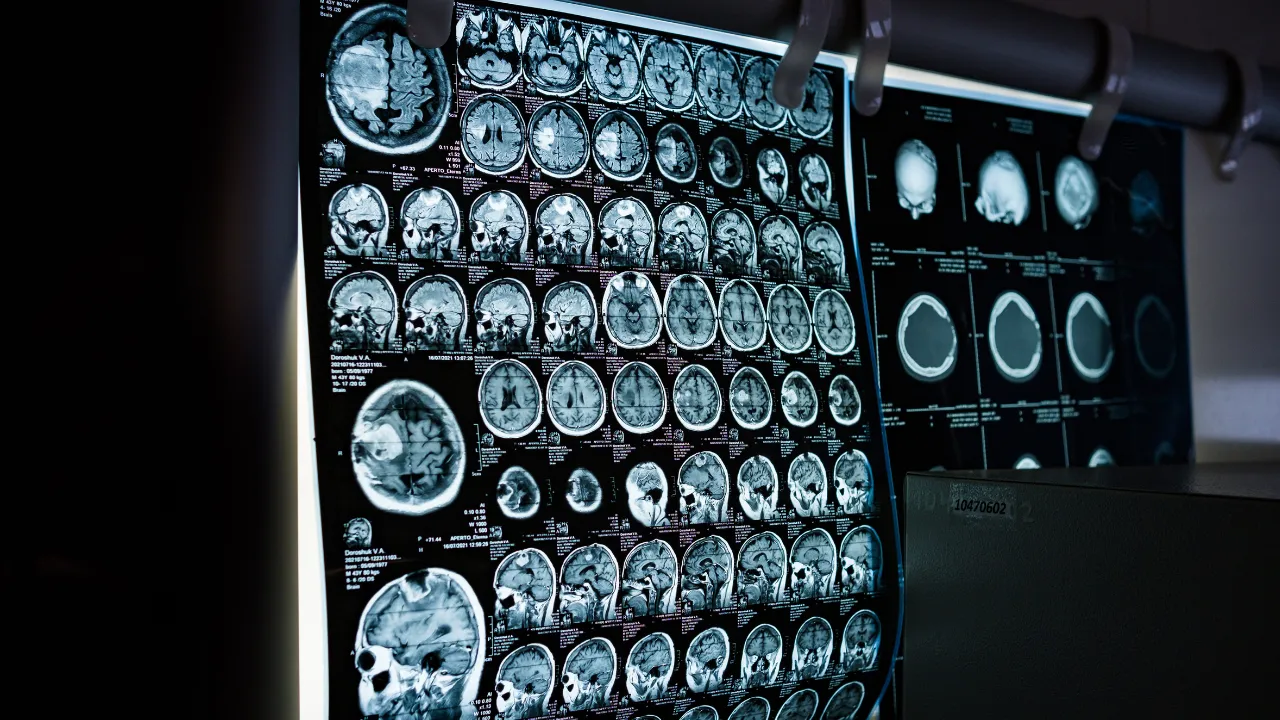

Aradan 3 hafta sonra Thomas’ın oyuncaklarıyla oynarken sağ elinin titremeye başladığını söyleyen anne, acil sağlık ekiplerine verdi. Hastanede yapılan MR ve ileri tetkikler sonucunda, Thomas’ın beyninin birçok bölgesine yayılmış agresif ve kötü huylu tümörler olduğu ortaya çıktı.

12 Eylül 2024’te yapılan MR’da tümörün omuriliğe ve beyin sapına yayıldığı belirlendi. Hastane, tedavinin durdurulacağını açıkladı. Thomas dokuz hafta sonra, hayatını kaybetti.